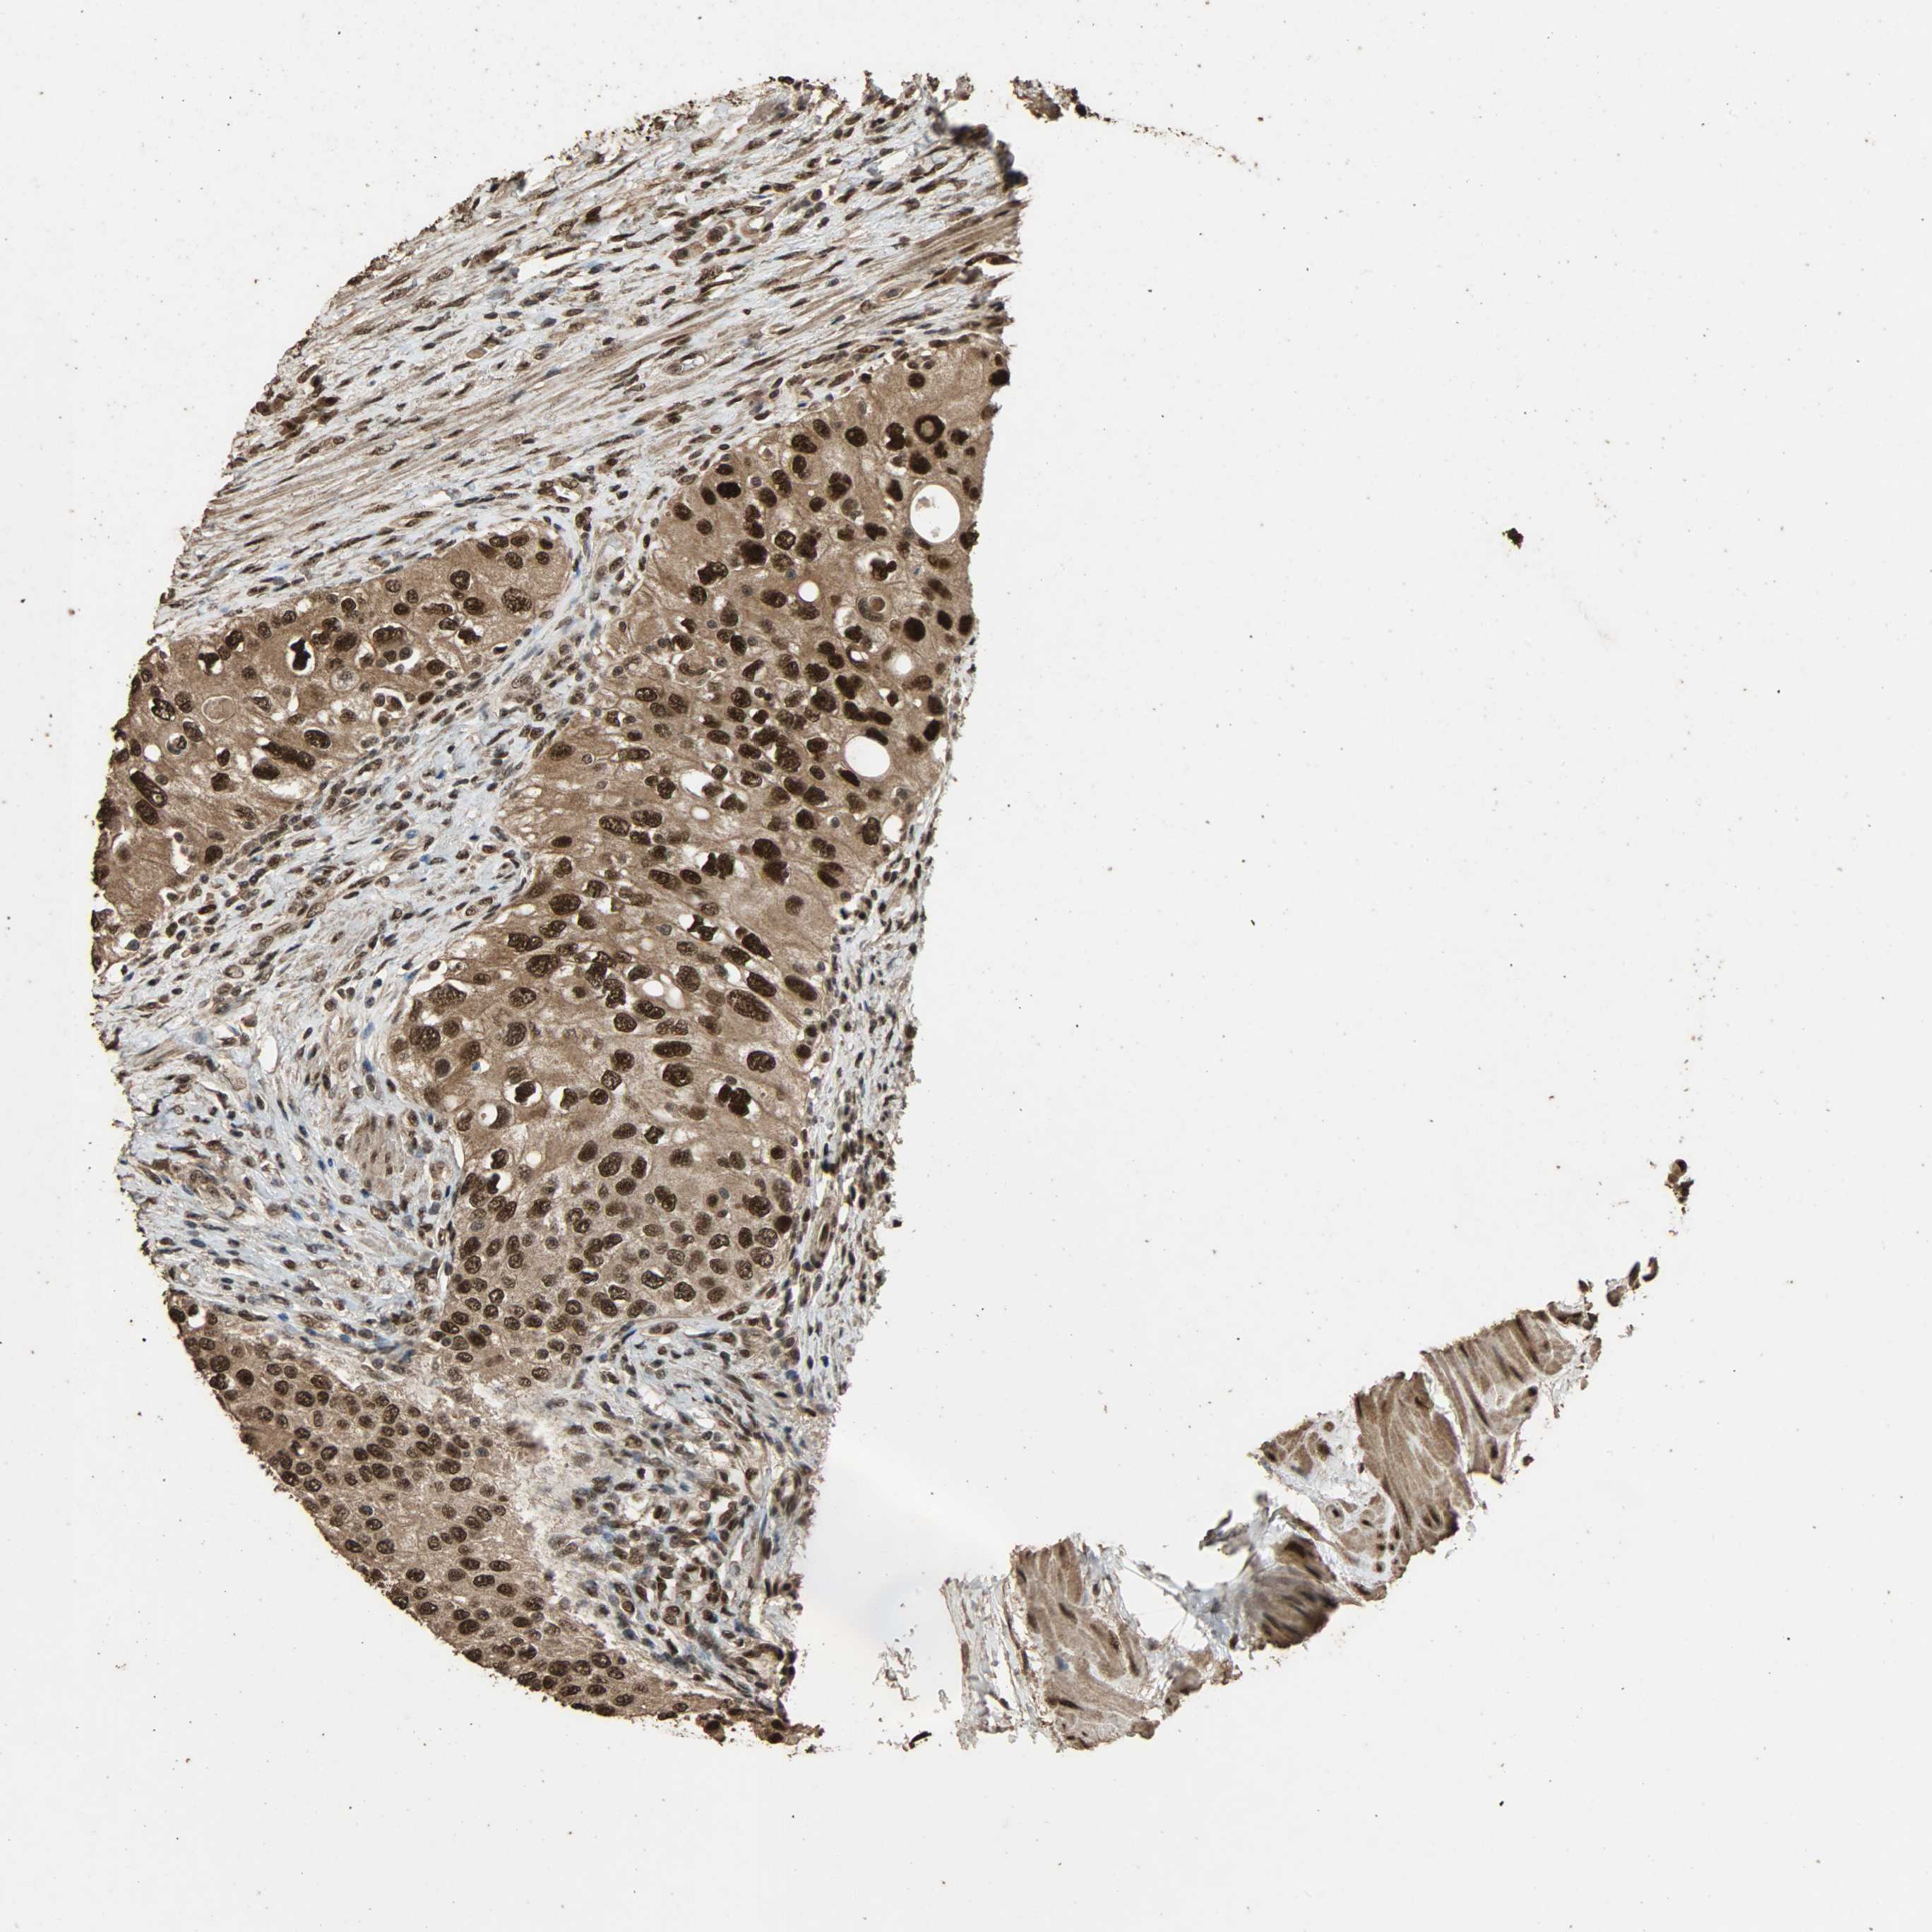

UROTHELIAL CANCER - Protein expressioni

A mouse-over function shows sample information and annotation data. Click on an image to view it in a full screen mode. Samples can be filtered based on level of antibody staining by selecting one or several of the following categories: high, medium, low and not detected. The assay and annotation is described here.

Antibody stainingi

Antibody staining in the annotated cell types in the current human tissue is reported as not detected, low, medium, or high, based on conventional immunohistochemistry profiling in selected tissues. This score is based on the combination of the staining intensity and fraction of stained cells.

Each image is clickable and will lead to virtual microscopy that enables deeper exploration of all samples and also displays staining intensity scores, fraction scores and subcellular localization as well as patient and tissue information for each sample.

Antibody HPA005559

Staining

High

Medium

Low

Not detected

Intensity

Strong

Moderate

Weak

Negative

Quantity

>75%

75%-25%

<25%

None

Location

Nuclear

Cytoplasmic/membranous

Cytoplasmic/membranous,nuclear

Urothelial carcinoma, High grade

Urothelial carcinoma, Low grade